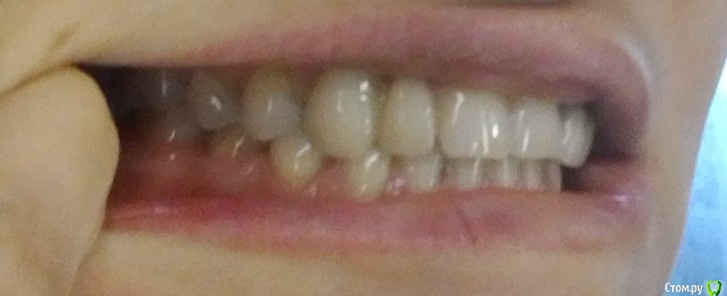

Здравствуйте, помогите определиться, пожалуйста. У меня нет верхних двоек. Стояли мосты с 15 лет. Сейчас один сняли, пока стоит временный. Я хотела сделать импланты, но врачи посмотрели КТ и сказали, что там очень мало места (3 и 5 мм), никак не воткнуть. Надо брекетами раздвигать место. Так вот я сходила к 3 ортодонтам и две сказали что брекеты нужны только на ВЧ, а одна что на обе. Я, конечно, хочу на одну - так проще и дешевле, а с деньгами у меня не густо. Но у меня зародилось сомнение - а, может, действительно надо на две делать? Что бы вы посоветовали?